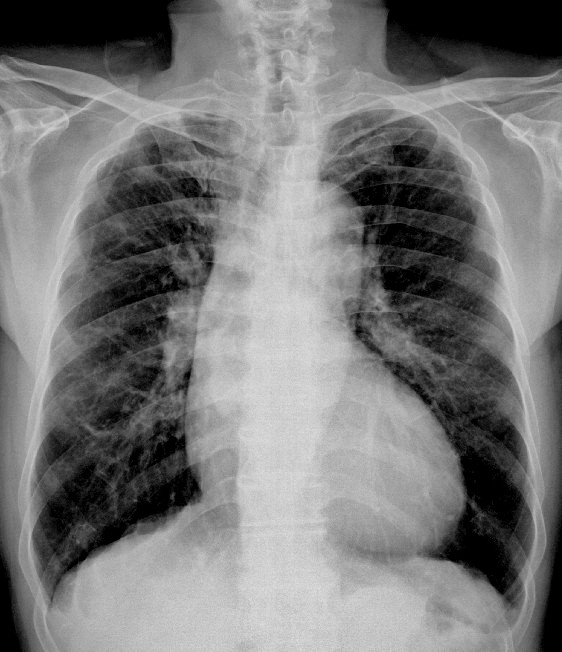

慢支病史20多年,咳痰,偶有带血,时常呼吸困难。

慢支,肺气肿,间质纤维化。右室段延长,心尖部圆顿上翘,提示右室增大,建议彩超。

1)考虑慢性支气管炎并肺气肿。2)心影呈“主动脉型”。

慢支炎、肺气肿、双肺间质纤维化,主动脉型心影。

慢支,肺气肿,右上肺纤维条索影,不排除结核病灶.还是ct检查.

慢支肺气肿,间质性纤维化,主动脉型心脏。